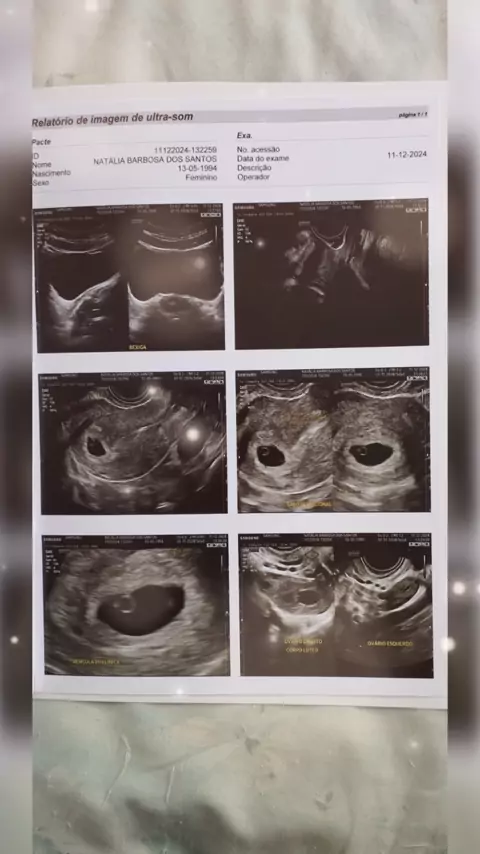

minha primeira ultrassom 🥰. um alívio saber que está tudo bem, que meu amor está crescendo😍❤️ #maedeprimeiraviagem #baby #presente #nenem #Meuamor